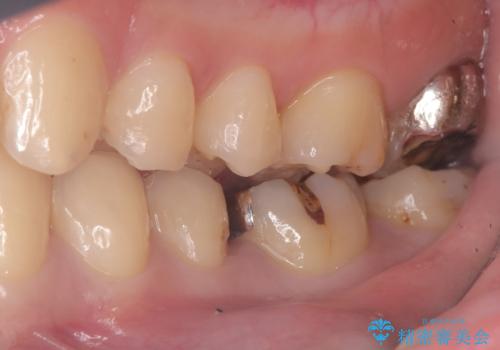

- 主訴:銀の詰め物が取れた、奥の銀の詰め物も一緒に白くしたい

保険適用のメタルインレーの脱離で来院されました。審美性、適合性、清掃性の観点から2本ともセラミックインレーでのやり替えとなりました。

保険適用のメタルインレーはセラミックやゴールドに比べるとプラークなどの汚れが付きやすく、また今回はそこまで大きなう蝕は広がっていませんでしたが、適合性に限界があるためインレーと歯質との境目で二次う蝕が発生する可能性が高くなります。